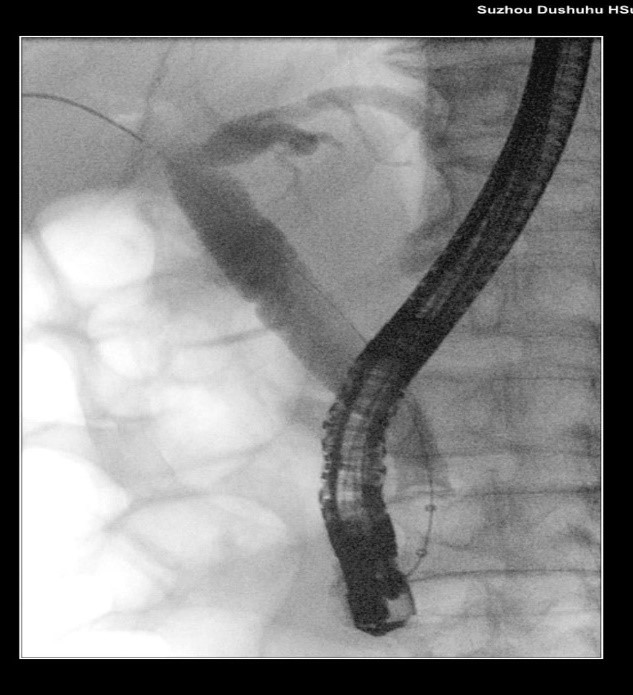

苏大附四院ERCP团队在手术中看到陈大爷的胆总管在结石的影响下已经宽达13mm,结石大小11*10mm,将十二指肠乳头切开并扩张后用取石球囊把结石取出,置入胆管支架使胆汁充分引流,顺利解除了胆道梗阻。

扩张取石